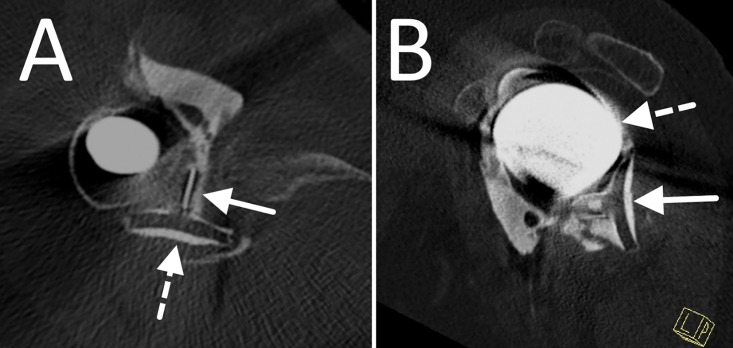

Glenoid component migration is a serious complication in total shoulder arthroplasty, causing 32% of failures and 7% of revisions. Detecting polyethylene loosening is challenging due to its radiolucency. We report a case of a 72-year-old woman with shoulder pain three years post-arthroplasty. Initial radiographs were unremarkable, but CT-arthrography revealed a displaced polyethylene spacer, rotated 90°, thus causing a mechanical block. Retrospective analysis of the X-rays showed the absence of the spacer in the expected position. Surgery restored functionality. This case highlights the diagnostic challenges of radiotransparent components with possible migration in unexplained post-arthroplasty shoulder pain. Teaching point: Verify glenoid component positioning in shoulder arthroplasties.